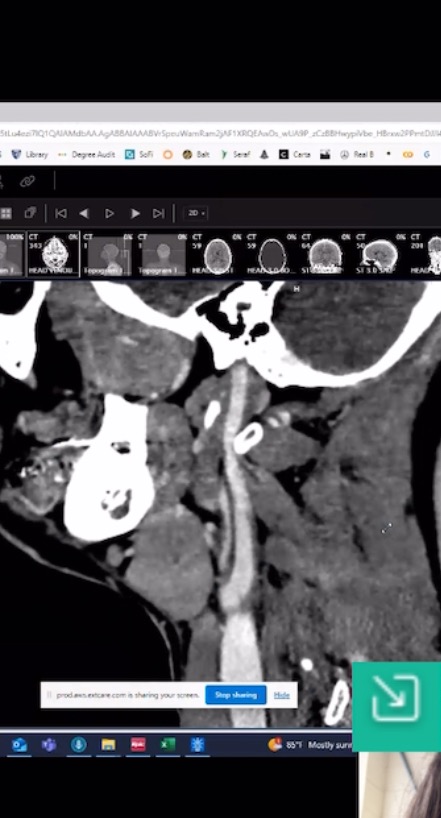

Turns out, brain surgery wasn't the end of my medical nightmares. Today, July 12 is the one year anniversary of my gamma knife radiation that was supposed to be a relatively mild procedure with a recovery time of about 2-7 days. The neurosurgeon and his team weren't able to retrieve the entire tumor resting somewhere in-between my pituitary gland, optic chiasm, and my brain during my brain surgery in January of '24. It was too risky and they did the best they could without a serious rise in the potential for me to bleed out and die. After the surgery, I recovered for about 3 weeks until I wasn't in extreme constant pain and at that point, felt pretty good about by after surgery symptoms. The doctors wanted to monitor me and do another MRI after three months to see the difference. The MRI showed that there was still a portion of the tumor that was left over and gamma knife radiation was recommended as the next treatment of choice.